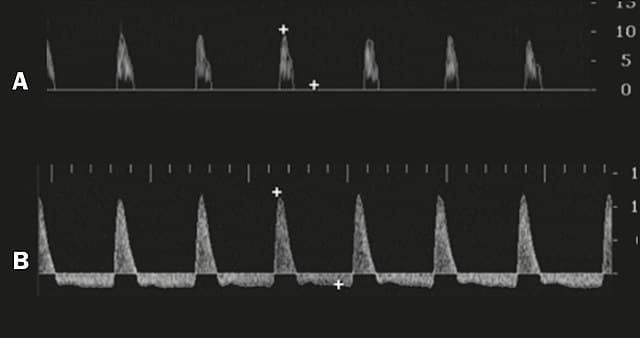

Estudio de tumescencia nocturna

Ayuda a separar la causa orgánica de la no orgánica. Se mide el número, duración y rigidez de las erecciones espontáneas nocturnas durante el sueño. Lo normal: ≥3 episodios, ≥10 minutos cada uno, con rigidez ≥70%